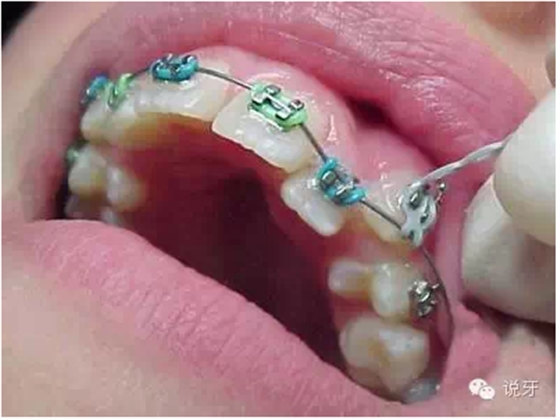

7、上牙套

最忐忑的時(shí)候到了。剛開始戴上牙套會(huì)有點(diǎn)不適感,有些可能還引發(fā)口腔潰瘍,牙齒也會(huì)有些酸痛感,這種狀況一般持續(xù)一周左右。戴上牙套后不宜吃有粘性、硬度大的食物。